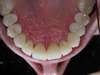

Nous avons reçu notre patient qui souffre de bruxisme intense et s'est errodé 3/4 mn de son étage inférieur.

Nous avons surélevé son occlusion par des onlays postérieurs pour dégager de l'espace antérieur et 6 couronnes antérieures ont été posées. Nous en avons éclairci la teinte globale des dents